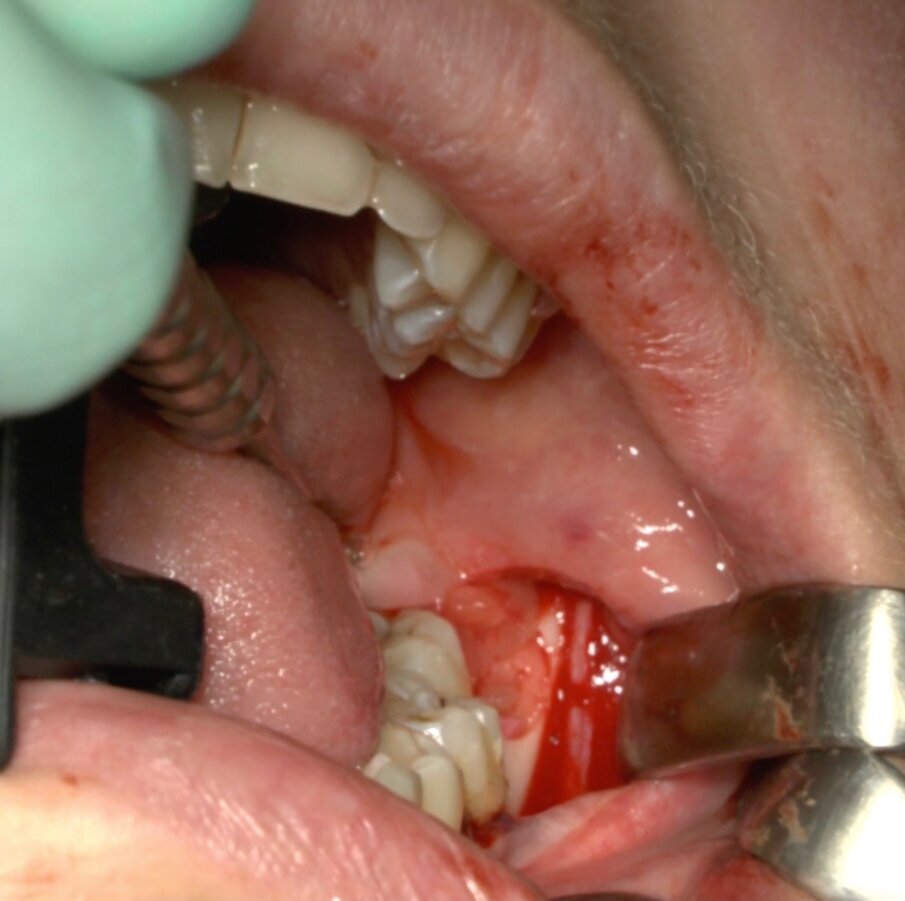

Ai pazienti viene prescritta una profilassi antibiotca con 2 gr di amoxicillina 1 h prima dell’intervento, si esegue quindi un anestesia di tipo tronculare con lidocaina senza vasocostrittore, poi infiltrazione di tipo plessica con adrenalina in corrispondenza del nervo buccinatore. Si scolpisce quindi un lembo a tutto spessore di tipo triangolare con incisione orizzontale alla base delle papille tra sesto e settimo ed incisione di scarico distale con andamento vestibolare (Figg. 1-4). Si procede con l’osteotomia che può essere eseguita con strumenti rotanti montati su manipolo retto oppure con terminale piezoelettrico con gli inserti dedicati. Qualora sia necessario si effettua l’odontotomia e la separazione radicolare con frese al carburo di tungsteno montate su turbina, quindi si esegue la lussazione e l’avulsione dell’elemento dentario. Si procede alla revisione della cavità alveolare con abbondante lavaggio con soluzione fisiologica, riempimento con collagene e sutura a punti staccati in seta 4/0. Il paziente viene dimesso con terapia analgesica ed antibiotica di supporto (Figg. 5-15).

Fig. 10_Cavità alveolare residua.